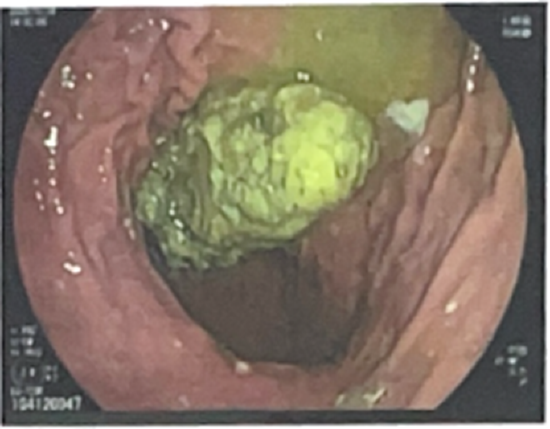

近期,消化内科接诊的这两位患者情况较为典型。一位是本院医生的母亲,另一位是二十多岁的年轻患者,他们均因腹痛、消化不良前来就诊。经胃镜检查,发现胃内存在巨大胃石。询问病史得知,两位患者都食用了柿子以及山楂这类食物。

方洒医生介绍,柿子和山楂中含有鞣酸和果胶,这些成分在遇到胃酸后,会使胃里的蛋白质变性,如同沙子和水泥混合,让胃内食物凝结成块。若食用量较大,这些块状物会逐渐增多,最终形成胃石。这两位患者的胃石体积较大,无法自行溶解。

针对这两位患者的病情,西安市红会医院消化内科采用了多种治疗方法。首先,通过内镜将碎石器以及圈套器送达胃内部,运用微创技术,像使用剪刀一样,将巨大的胃石切碎成小块,促进其从胃内排出。对于比较坚硬、体积较小的胃石碎片,必要时会将其取出。